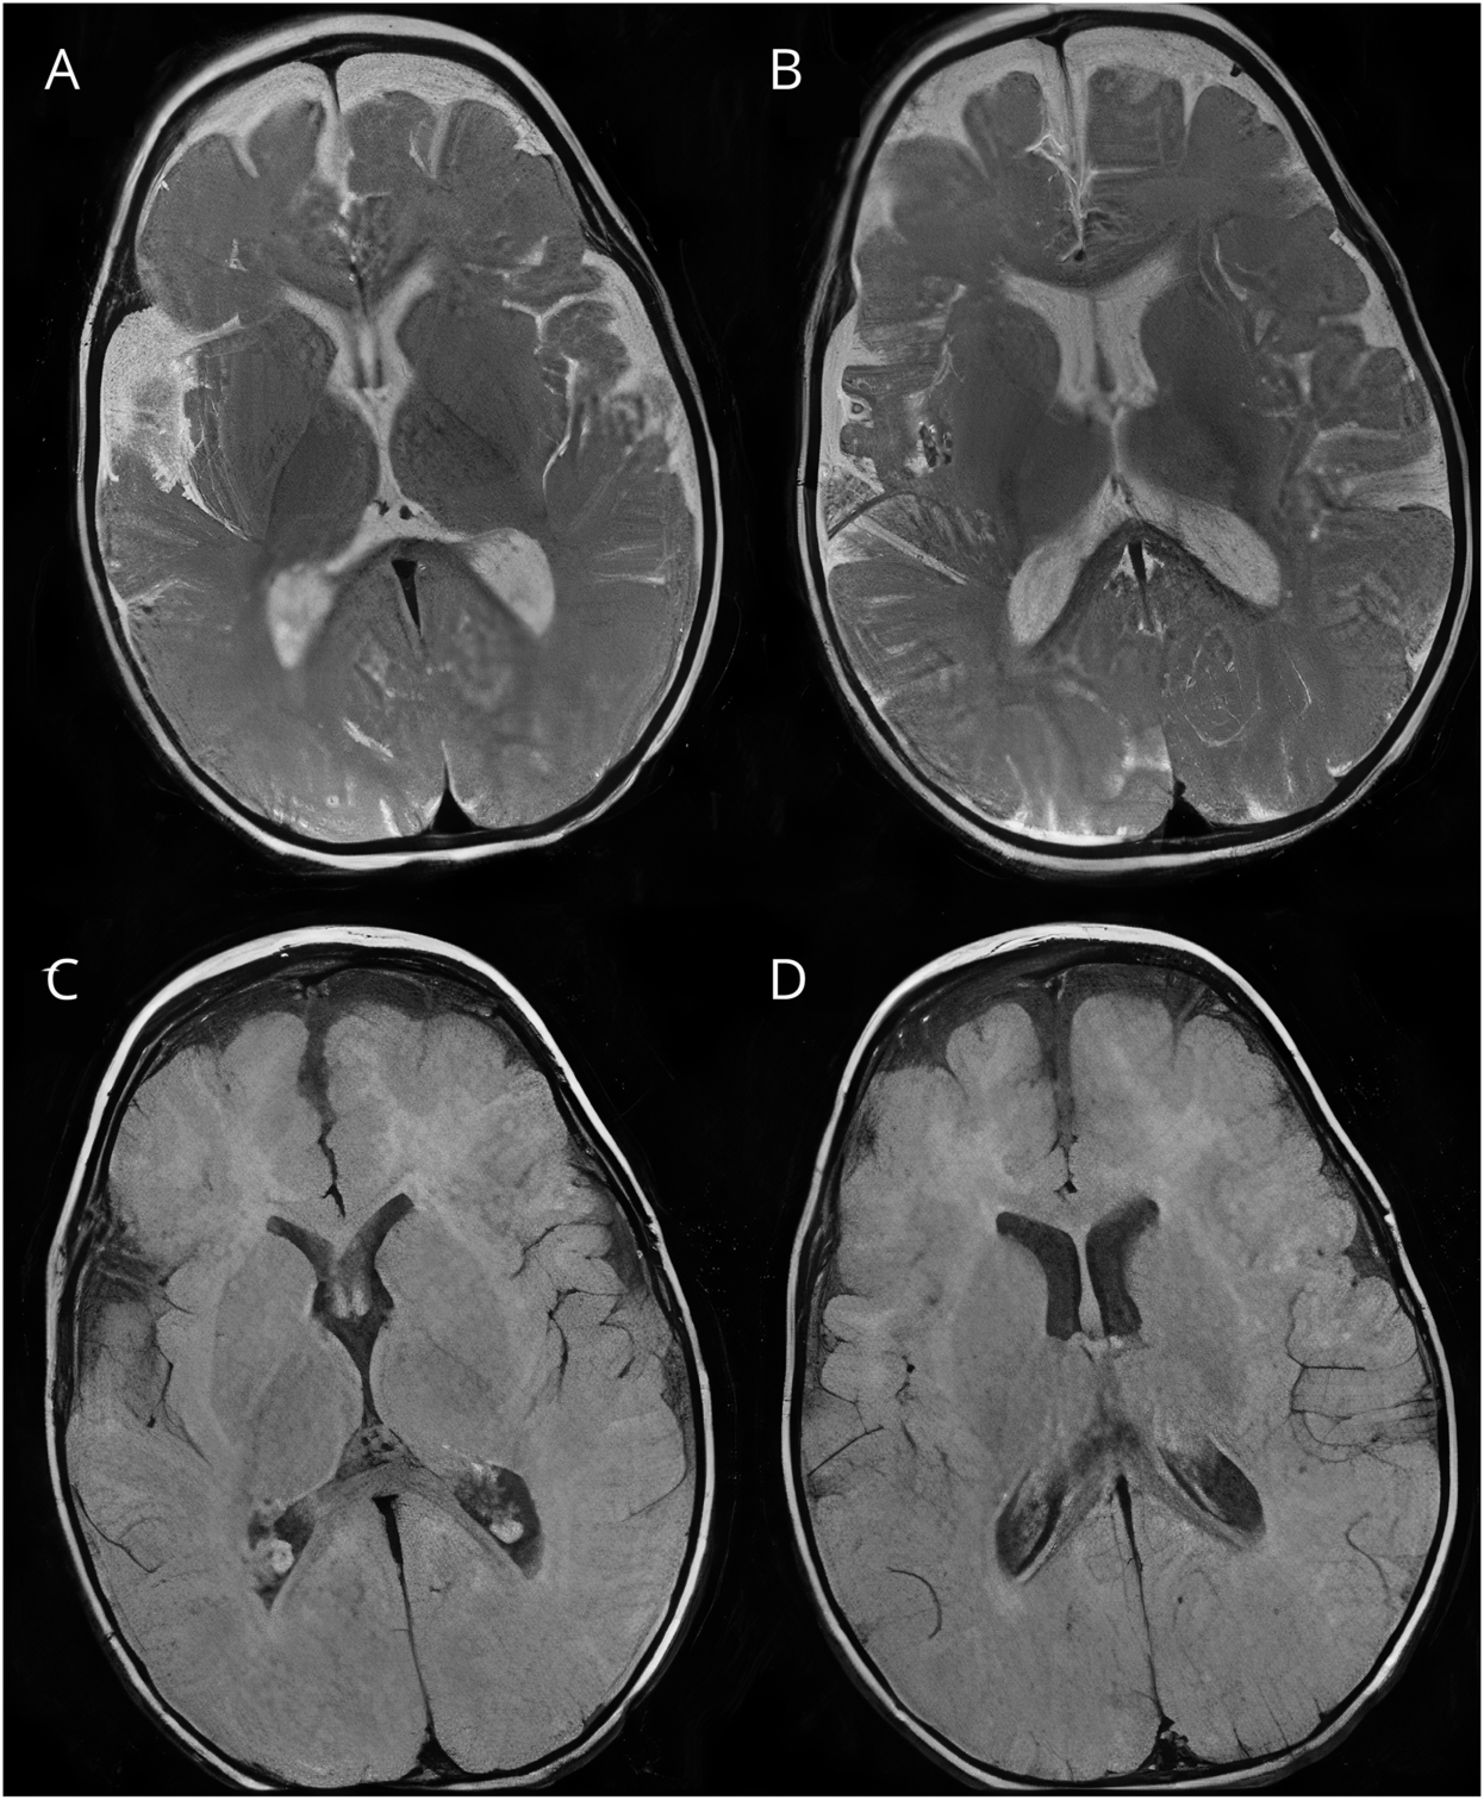

一名5岁女孩,面部特征异常,斜视,水平眼震,张力减退,有嗜睡史,癫痫发作和发育迟缓,开始出现全身性复杂运动障碍。临床表现为混合性多动性运动障碍,包括舞蹈症、肌张力障碍、肌阵挛和手部定型。广义抽搐的出现,与那些复杂的动作穿插在一起,就像定格动画(视频1),类似于动画技术,在动画技术中,物体以小幅度的物理操作和逐帧拍摄。脑部核磁共振显示轻度额叶皮质萎缩(数字).进行遗传调查,进行CGH阵列,在PURA基因中发现一个致病变异arr[GRCh37]5q31.2q31.3(139033279_140058893)x1,与PURA综合征相容。1在有全面发育迟缓的婴儿中出现复杂的多动力运动障碍可能是诊断PURA综合征的重要线索。如果不进行遗传研究,受影响的患者可能被误诊为动力障碍脑瘫。2